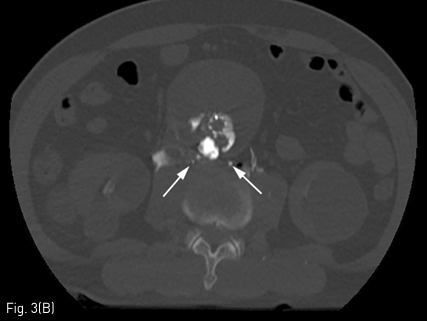

초음파 유도 하에 우측 내경정맥을 천자하여 Rosch-Uchida transjugular liver access set (Cook, Bloomington, IN, USA) 에 포함된 10F sheath 를 하대정맥에 삽입한 뒤 sheath tip 은 제3 요추의 상연에 위치시켰음. 이후 set 에 포함된 14G stiffening cannula에 Rosch-Uchida needle 을 삽입하고 투시의 전후 및 측면 영상을 이용하여 needle의 위치와 천자방향을 확인한 뒤 하대정맥에서 대동맥류를 직접 천자하였음. 이후 needle tip을 동맥류내의 제3-4 요추사이공간 level 의 제3 허리동맥 기시부로 위치시키고 혈관조영술을 시행하였음. 혈관조영술에서 type II endoleak 의 원인이 되는 제3 허리동맥이 관찰되었으며(Fig. 2), 이를 N-butyl cyanoacrylate 와 lipiodol 을 1:2 로 혼합한 용액 4.5mL 를 주입하여 색전술을 시행하였음. 시술 중 시행한 Fluoroscopy 와 시술 후시행한 CT에서 모두 표적인 제3 허리동맥 내부에 lipiodol 이 차 있는 것을 확인한 뒤 시술 종료하였음(Fig. 3)

Fig 2

Angiography after direct puncture of aneurismal sac via transcaval approach revealed contrast filling within the aneurismal sac communicating with lumbar arteries (black arrows)